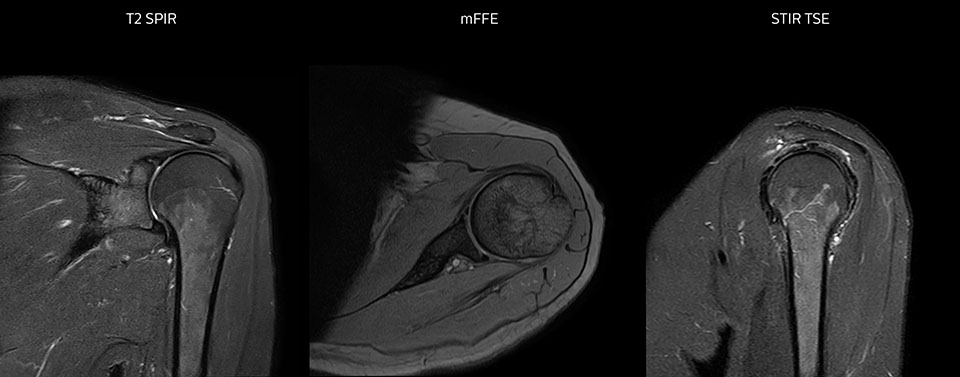

Shoulder MRI with high quality, large coverage

The Prodiva shoulder coil is very flexible and has large coverage, which makes good positioning easier, and that contributes to the superb image quality and high SNR that we get in our shoulder exams.

Scan time 2:55 min, FOV 160 mm, acq voxels 0.55 x 0.83 x 3.0 mm.

Scan time 4:19 min, FOV 160 mm, acq voxels 0.55 x 0.80 x 3.0 mm.

Scan time 2:50 min, FOV 160 mm, acq voxels 0.70 x 0.99 x 3.0 mm.

Shoulder MRI with high quality, large coverage

The Prodiva shoulder coil is very flexible and has large coverage, which makes good positioning easier, and that contributes to the superb image quality and high SNR that we get in our shoulder exams.

Scan time 2:55 min, FOV 160 mm, acq voxels 0.55 x 0.83 x 3.0 mm.

Scan time 4:19 min, FOV 160 mm, acq voxels 0.55 x 0.80 x 3.0 mm.

Scan time 2:50 min, FOV 160 mm, acq voxels 0.70 x 0.99 x 3.0 mm.